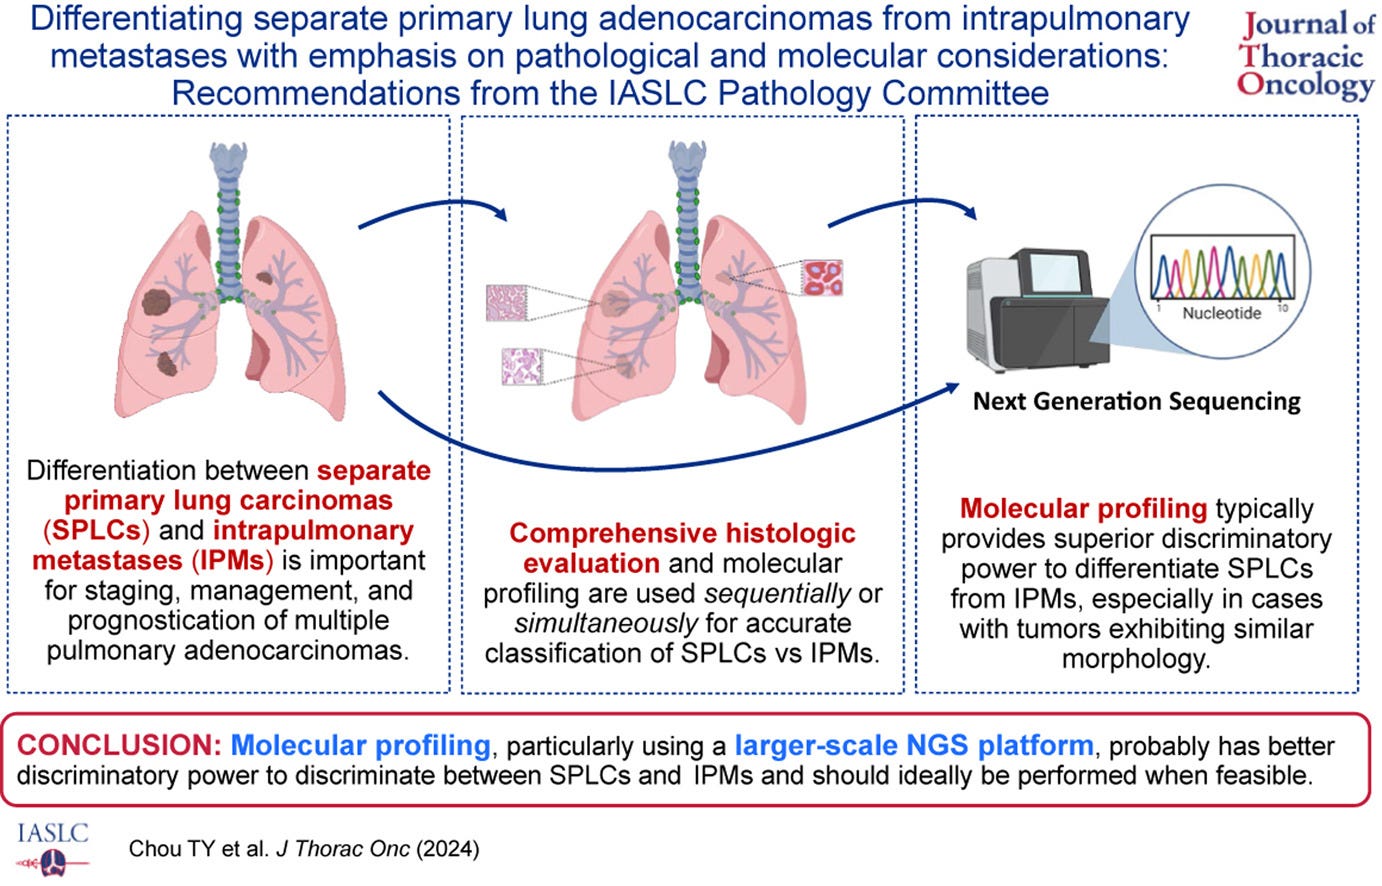

🫁 Ako odlíšiť primárny adenokarcinóm pľúc od intrapulmonálnych metastáz?

Pokrok v zobrazovacích technikách, ako je nízkodávková výpočtová tomografia (CT), umožňuje lepšiu detekciu viacerých pľúcnych nádorových uzlov (MPTN).

Rozlíšenie medzi samostatnými primárnymi adenokarcinómami pľúc (SPLC) a jeho intrapulmonálnymi metastázami (IPM) je kľúčové nielen pre správne stanovenie štádia ochorenia, ale aj pre efektívne plánovanie liečby a presnejšiu prognózu.

🔬 Histopatológia a molekulárna analýza – kľúč k presnej diagnostike!

Histopatologické vyšetrenie je základom rozlíšenia SPLC od IPM. Rozdiely v štruktúre nádoru a cytológii často ponúkajú zásadné vodítka.

Napriek tomu môže byť táto metóda subjektívna a náchylná na rozdiely medzi hodnotiacimi patológmi. Preto sa stále viac uplatňujú nové molekulárne technológie, ako je sekvenovanie novej generácie (NGS), ktoré prinášajú väčšiu presnosť a spoľahlivosť.

Analýza mutácií v určitých génoch (napr. EGFR, KRAS) a tumor-supresorového génu (TP53), poskytuje presnejší obraz o pôvode nádorov – rôzne typy mutácií medzi nádorovými uzlami jednoznačne naznačujú SPLC.

📑 Nový 4-stupňový algoritmus od IASLC

Medzinárodná asociácia pre štúdium rakoviny pľúc (IASLC) navrhuje štruktúrovaný algoritmus, ktorý kombinuje histologické a molekulárne prístupy:

Počiatočné histologické hodnotenie na základe štruktúry a cytológie nádoru.

Posúdenie histologických výsledkov inými patológmi („peer review”), ak sú v nich nezrovnalosti.

Jednoduchá molekulárna analýza na identifikáciu hlavných mutácií.

Pokročilé molekulárne techniky, ako NGS, pre riešenie nejasných prípadov.

🧐 Prečo na tom záleží?

Správna diferenciácia medzi SPLC a IPM má priamy dopad na liečbu pacienta.

Pri SPLC sa nádory liečia ako samostatné jednotky.

Na druhej strane, IPM sú zvyčajne indikáciou pre systémovú liečbu.

Navyše prognóza pacientov so SPLC je často lepšia, ak sa diagnostika vykoná presne a včas.